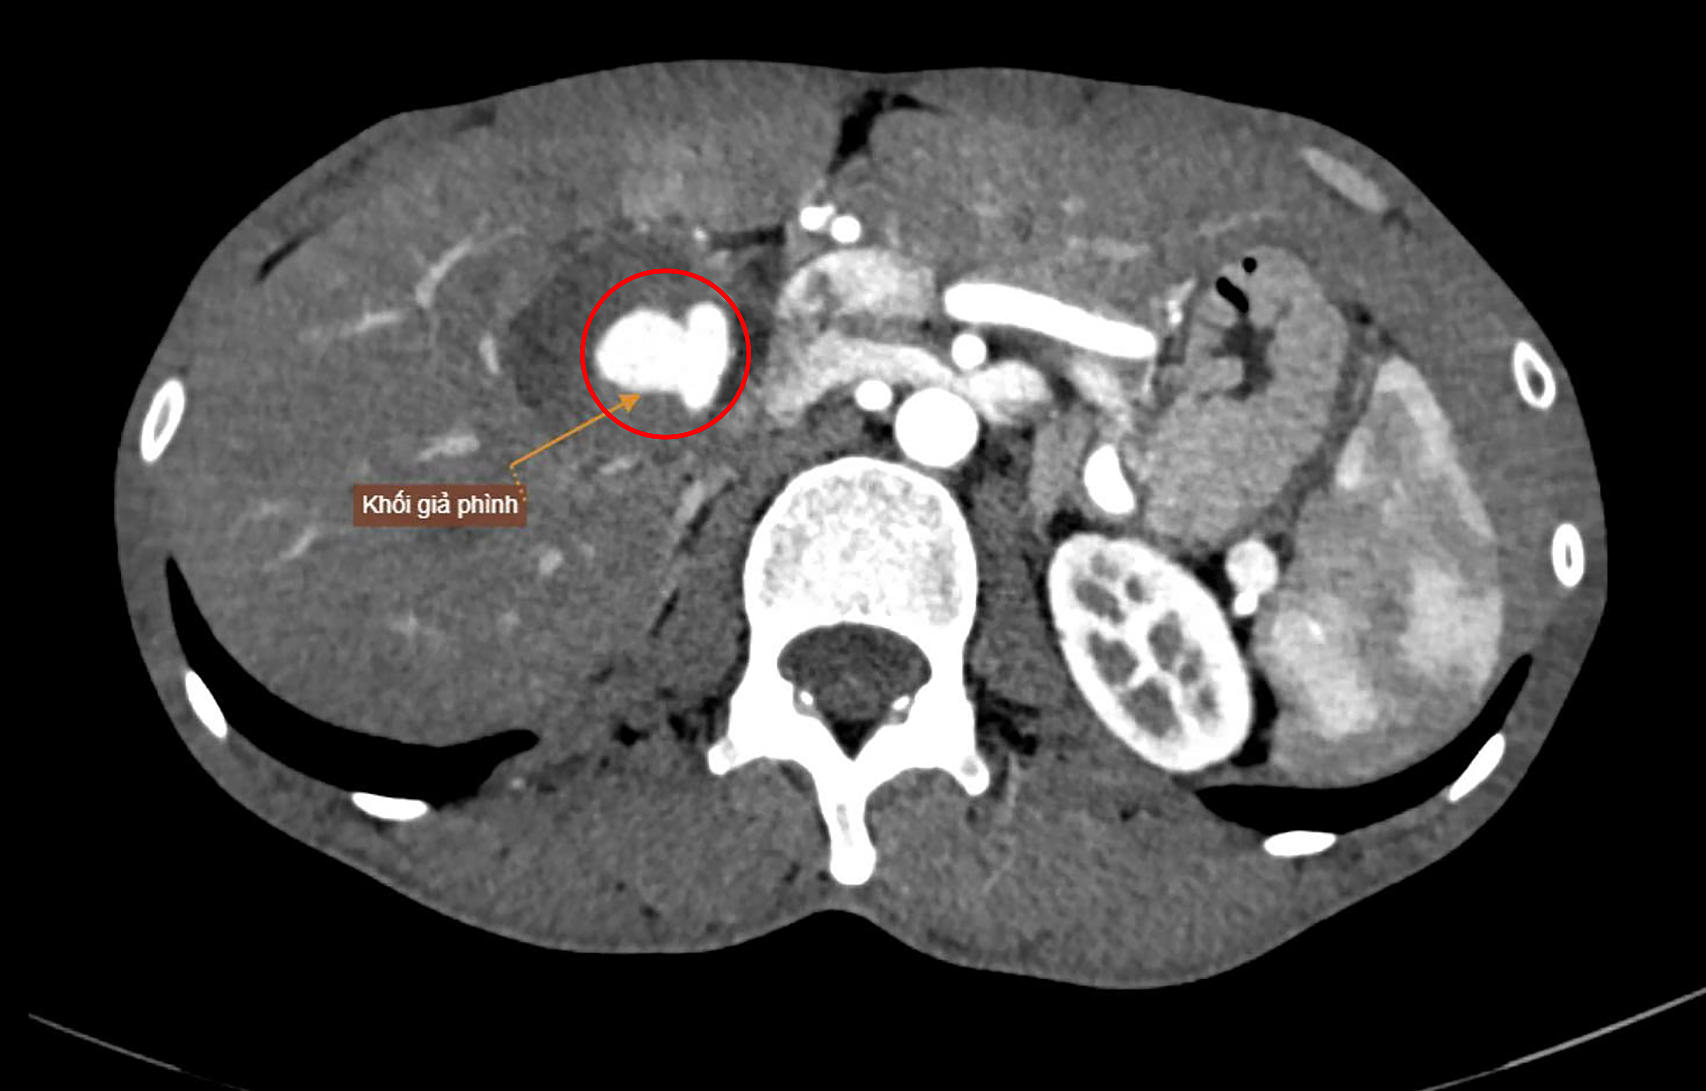

A contrast-enhanced abdominal CT scan of Mr. Thoi at Tam Anh General Hospital in Ho Chi Minh City revealed multiple pseudoaneurysms in various locations, including the hepatic artery, stomach region, kidneys, and lumbar area. Notably, a large pseudoaneurysm measuring 40x40x65 mm was found in the hepatic hilum, originating from a branch of the right hepatic artery. This mass was compressing adjacent structures, causing impaired perfusion of the liver parenchyma and compressing the right renal vein.

A large pseudoaneurysm with rupture risk shown on a CT scan. *Photo: Tam Anh General Hospital* |